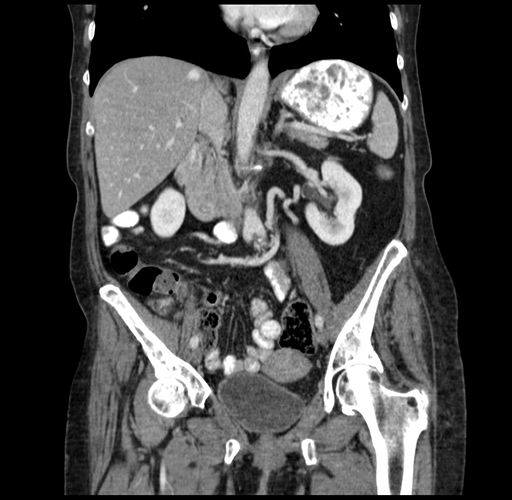

Axial Venous

Coronal Venous